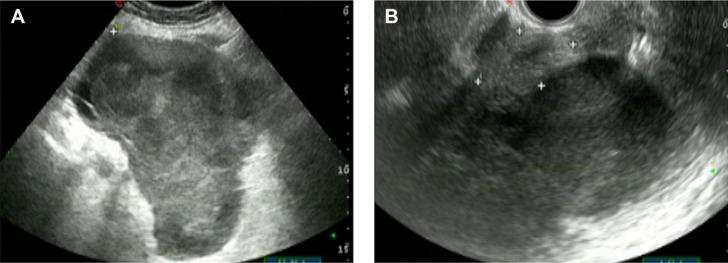

Primary malignant lymphoma of the uterus and broad ligament is rare. Here, we present a rare case of primary diffuse large B-cell lymphoma (DLBCL) of uterus and broad ligament in a 63-year-old female. The patient presenting with lower abdominal distention was referred to our hospital. Subsequent abdominal and pelvic ultrasound revealed the presence of a large mass, which was highly suspected as subserosal uterine leiomyoma. A large tumor was found with unclear boundary with right posterior wall, broad ligament and bilateral adnexa during surgery. Her uterus and the tumor of a broad ligament and bilateral adnexa were all excised as a result. Postoperative pathological examination showed DLBCL in uterus and broad ligament. Further examinations excluded metastatic diseases, which supported the diagnosis of primary DLBCL of the uterus and broad ligament. The patient received six cycles of R-CHOP (21 days) regimen. During the 8 months follow-up, no evidence of disease recurrence was identified. As the prevalence of primary extranodal lymphoma is increasing, the details of this rare case may highlight the importance and facilitate treatment of similar diseases. A summary focusing on the presentation and prognosis as well as a review of current management is also discussed.

原发性子宫和阔韧带恶性淋巴瘤较为罕见。在此,我们报告一例63岁女性原发性子宫和阔韧带弥漫性大B细胞淋巴瘤(DLBCL)的罕见病例。该患者因下腹胀就诊于我院。随后的腹部和盆腔超声检查发现一个大肿块,高度怀疑为浆膜下子宫肌瘤。手术中发现一个大肿瘤,与右后壁、阔韧带和双侧附件边界不清。因此,切除了她的子宫、阔韧带肿瘤及双侧附件。术后病理检查显示子宫和阔韧带存在DLBCL。进一步检查排除了转移性疾病,支持原发性子宫和阔韧带DLBCL的诊断。患者接受了六个周期的R-CHOP(21天)方案治疗。在8个月的随访中,未发现疾病复发迹象。由于原发性结外淋巴瘤的患病率在增加,该罕见病例的细节可能会凸显类似疾病的重要性并有助于其治疗。本文还讨论了该病例的临床表现、预后总结以及当前治疗方法的综述。